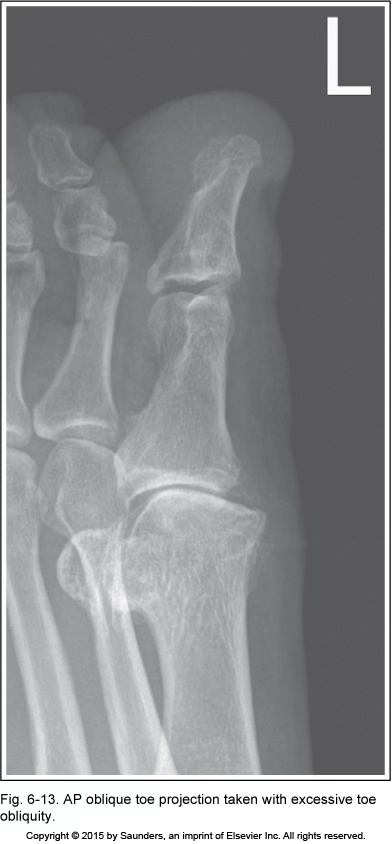

AP oblique toe

inadequate toe obliquity

excessive toe obliquity